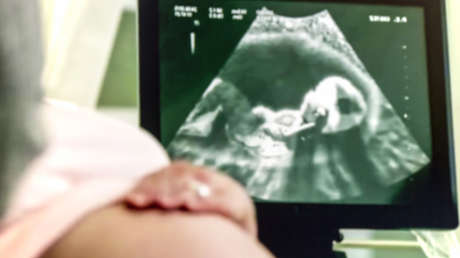

Bennett, de 37 años, quien fue operado en la mitad superior de su cuerpo, pero no en los genitales, finalmente decidió intentar y, poco después, inició el proceso de gestación de forma natural. "Siempre supe que existía la posibilidad de que mi cuerpo lograra el embarazo, pero no era algo que quisiera hacer hasta que aprendí a separar la función de mi cuerpo de cualquier noción de género", confesó el hombre en una conversación con DailyMail.

En octubre de 2020, Bennett dio a luz a su hijo Hudson mediante cesárea. Sin embargo, mientras estaba en el hospital, el personal médico desconocía su género, llamándolo "mamá". "Incluso con una barba completa, un pecho plano y un marcador de género masculino en toda mi identificación, la gente no podía evitar llamarme 'mamá', 'madre' o 'señora'", relató, agregando además que "nada de estar embarazado" le pareció "femenino".